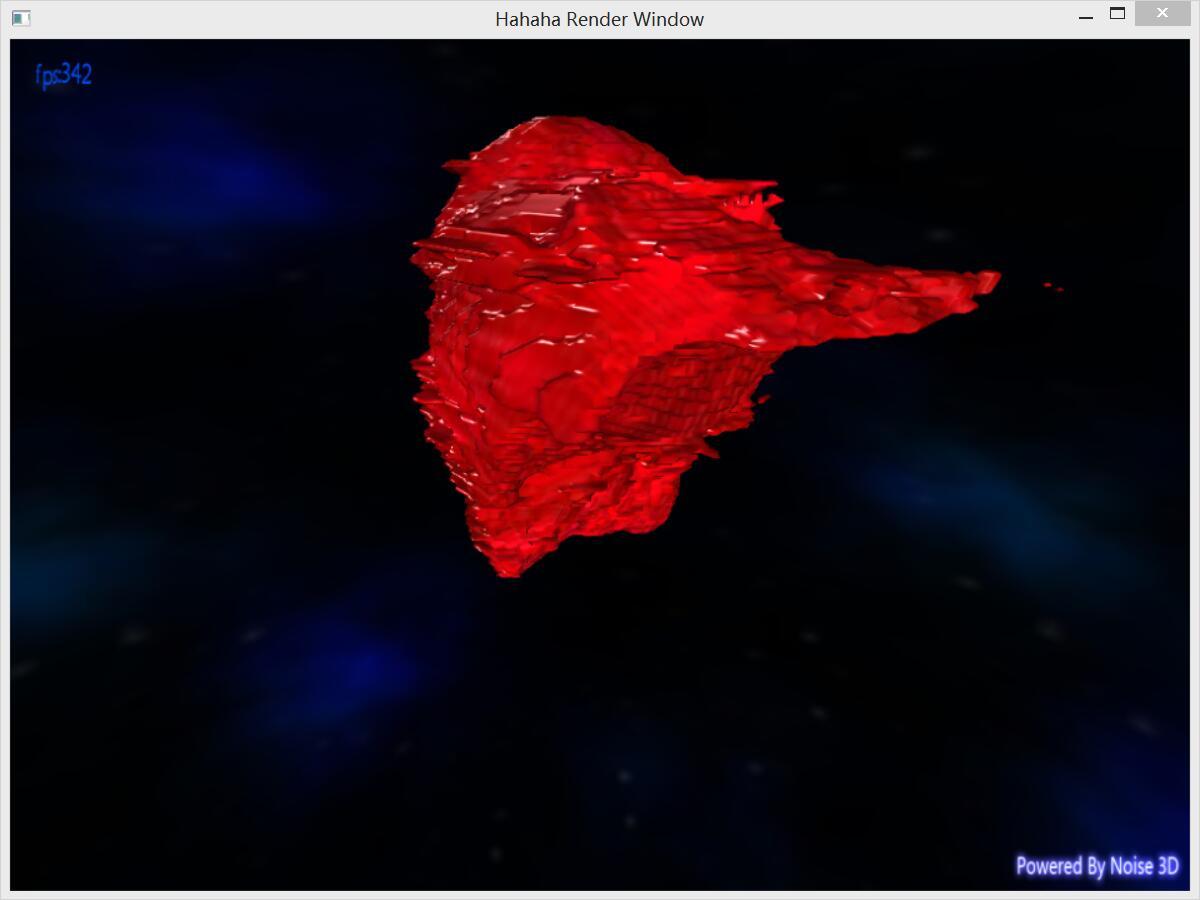

4, MarchingCube三维重建效果图

我的天,丑的吓人!但是这个丑讲道理是不能甩锅给MarchingCube的,要怪就怪图像识别做的不怎么样:)。(但在MarchingCube算法生成的模型还是比较多的明显锯齿)。